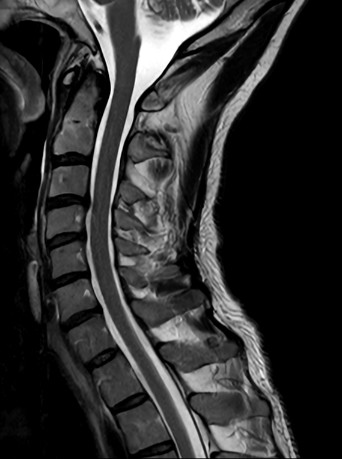

High quality Cervical Spine imaging with SmartSpeed Precise